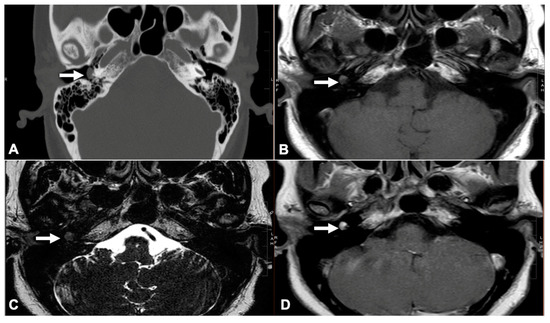

2.2. Glomus Tympanicum Evaluation